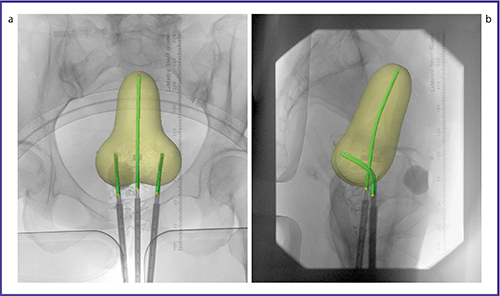

●治療計画

当院ではアプリケータ留置後,直交する2方向のX線写真を撮影し,これを治療計画装置に転送して治療計画を作成している(図4)。計画装置上でアプリケータの位置,投与線量を規定する標的規準点(子宮頸癌の場合,A点と呼ばれる),直腸および膀胱の線量評価基準点などを画像上に入力していく。なお,A点,直腸および膀胱の線量評価点は,ICRU Report 384)の勧告に基づき決定している。線源配置については,施設内での標準化を図るべく,一定の取り決めの下に行っている。例えば,子宮頸癌の場合は,マンチェスター法に準じて作成された標準線源配置パターンに基づいて線源配置を計画する。線量評価基準点の線量を評価し,必要に応じて適宜線源配置を調整する。計画が完成したら,治療装置にデータを転送する。複数のスタッフによるダブルチェックを経て,治療を開始している。

図4 直交する2方向のX線写真により作成された腔内照射計画例

a:正面像 b:側面像